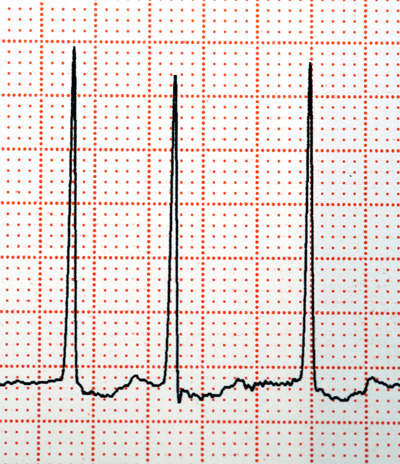

Illustrasjonsfoto: Science photo/NTB scanpix